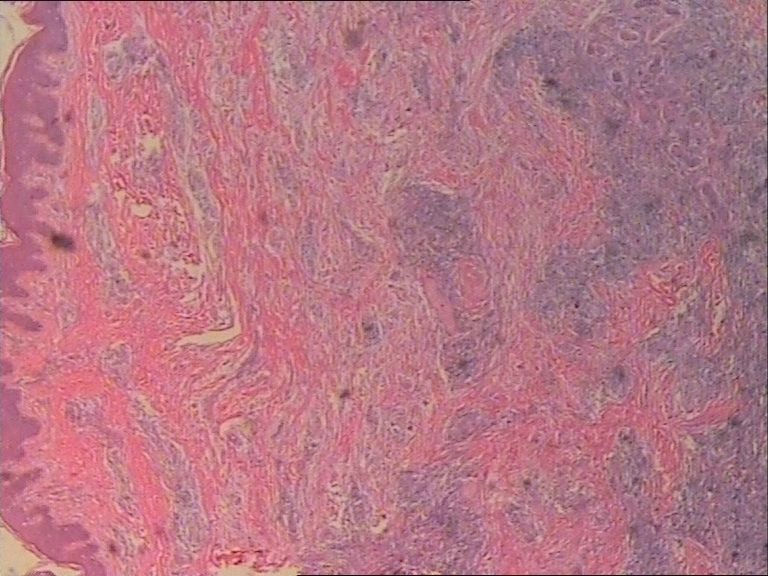

表皮下肿块FNAC一例,体现了该诊断手段的优势。

患者 女 47岁 腰部皮下肿块5x4cm,皮肤表面灰褐色,无隆起,无压痛。体格检查无其他异常。

• 表皮下肿块FNAC一例,体现了该诊断手段的优势。图1

图1

诊断是Rosai-Dorfman病。

是的,单核及多核组织细胞是本病不特异但恒定的特点。

涂片内见较多组织细胞和多核巨细胞。肉芽肿性炎。